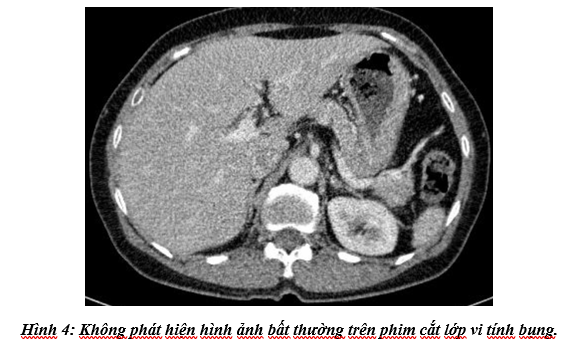

Cắt lớp vi tính bụng: Không phát hiện tổn thương bất thường.